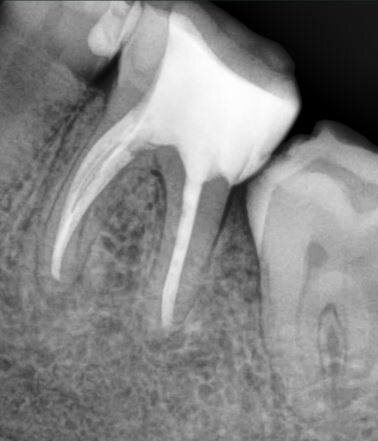

Через 6 месяцев после начала лечения наблюдалось значительное улучшение: уменьшение очага поражения и восстановление состояния десны. Рентгенологические исследования показали признаки регенерации костной ткани.